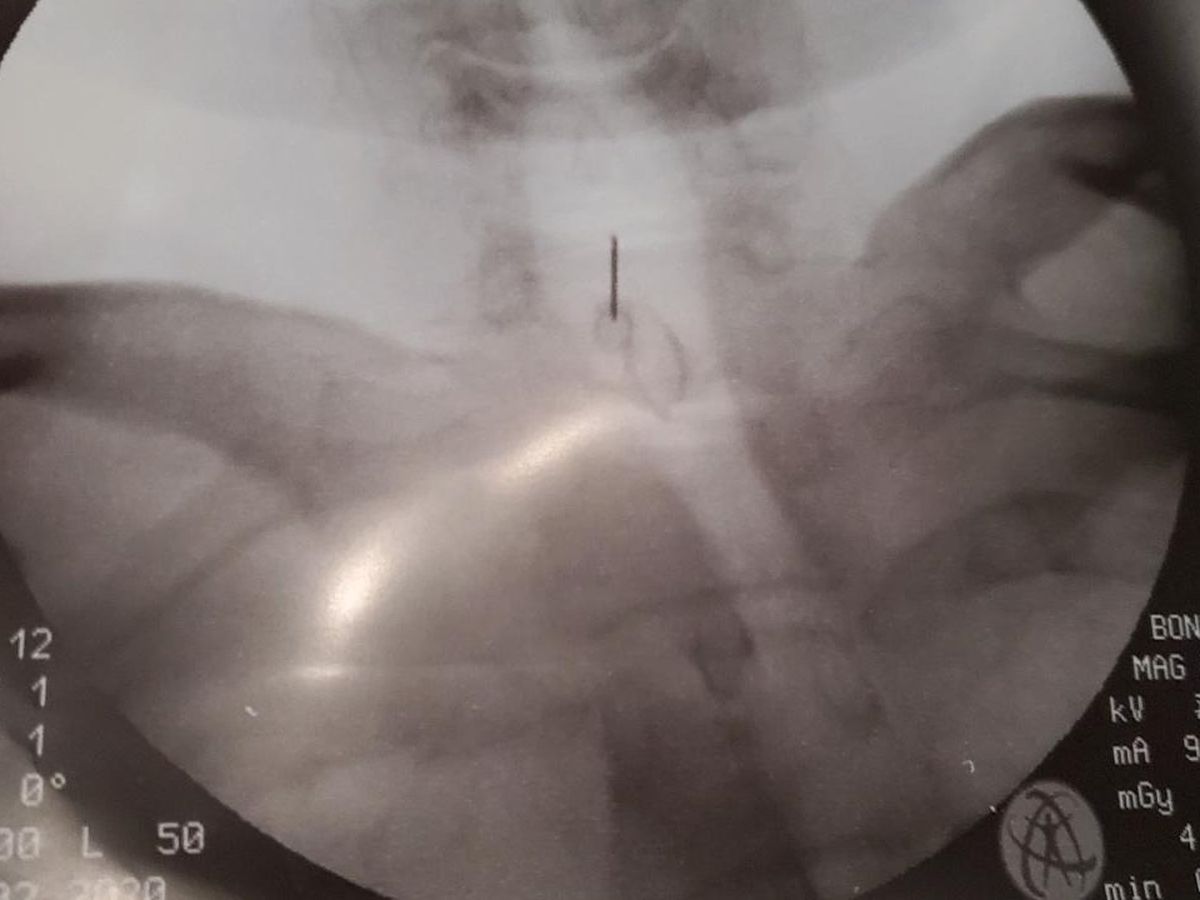

The photo I list on here is where the Dr injected a drug into my spine to help ease the pain "it did not work".